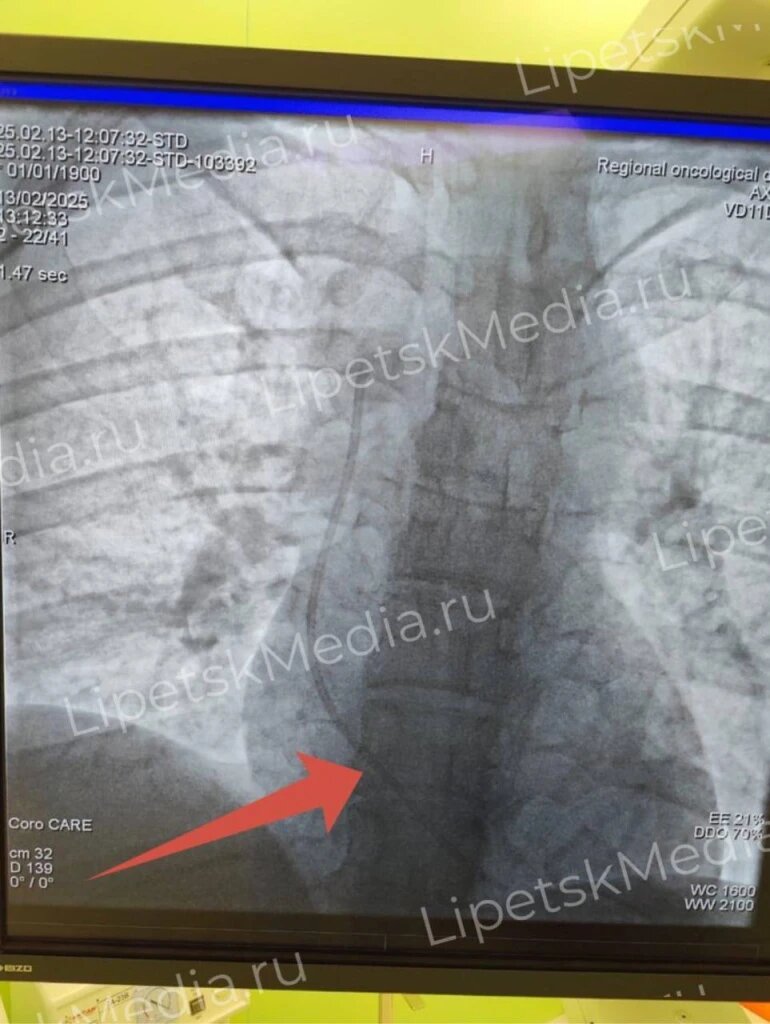

Катетер вытащили из сердца онкобольной женщины липецкие врачи

В Липецкой областной больнице успешно провели сложную операцию – из сердца 31-летней пациентки извлекли фрагмент катетера, который мог привести к серьёзным последствиям. Ранее женщине установили специальный катетер для постоянного введения препаратов. Со временем часть устройства отломилась и с током крови попала в камеры сердца.

Удалить фрагмент катетера удалось без открытой операции. Эндоваскулярный хирург Владимир Анисимов провёл вмешательство через сосуд, аккуратно достал инородное тело и не повредил сердце. После процедуры самочувствие пациентки улучшилось, угрозы жизни больше нет, сообщили в министерстве здравоохранения Липецкой области.